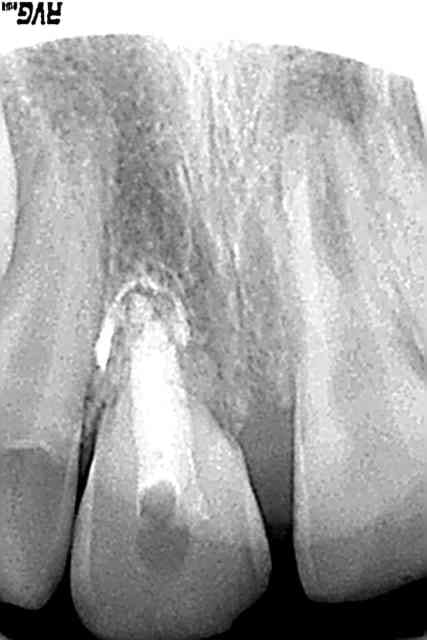

02/07/2008 à 00h04

dernières radios

11 pas de changement semble t'il:pourvu que cela dure

21 l'apex se ferme malgré un MTA qui aurait pu aller un poil plus loin

mais sniff je n'en verrais pas plus:il part à La Reunion

patvat si tu le récupères,merci de mettre la suite